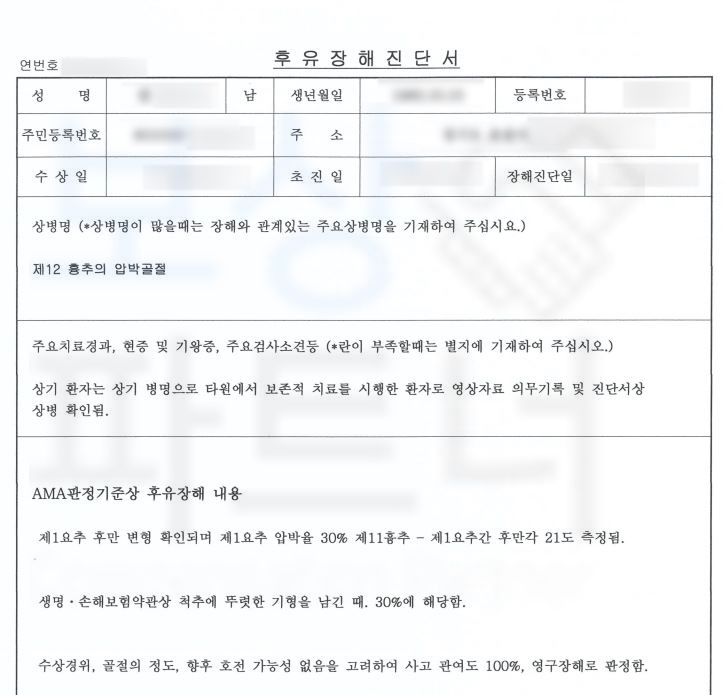

환자분은 이미 자신이 가입한 보험을 통해 실비, 입원비, 골절진단비 등등의 비교적 준비하기 서류들을 챙겨서 이미 보험금을 받으신 상황이셨어요. 후유장해 보험금은 자신의 신체에 남은 장해를 약관에 근거해 객관적이고 올바르게 평가하는 게 우선시됩니다.

이후 진단된 장해에 대해 대형 보험사를 상대로 장해의 적정성을 증명하는 과정이 필요하죠. 때문에 환자분은 보상 파트너에 연락 주셨고 보상 파트너는 환자의 영상 CD, 보험증권 의무 기록 등을 받아 분석하였습니다.

환자의 흉추12번 척추골절 장해는 무려 뚜렷한 기형 30% 영구 장해에 해당하였습니다. 이후 흉추 12번 척추골절 장해에 대한 적정성을 증명하기 위해 손해 사정서 및 증빙자료를 각 보험사에 송부하였고 보험사에서도 조사관을 배정하여 내부 자문 및 의료자문을 시행하며 환자의 장해에 대한 면밀한 조사를 진행하였습니다.

하지만 보상 파트너의 적절한 대응으로 흉추12번 척추골절 환자는 뚜렷한 기형 장해 모두 인정받아

후유 장해 4억 원 담보의 30% 지급받을 수 있었습니다.